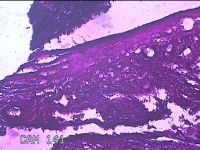

右侧卵巢囊肿及畸胎瘤

右侧卵巢囊肿破裂 右侧卵巢畸胎瘤

下腹痛30分钟。

灰白暗红色囊性肿物4.5x3x0.8cm一个,表面糜烂,因已切开,内容物已流失,内见大量油脂,囊壁厚约0.1cm。